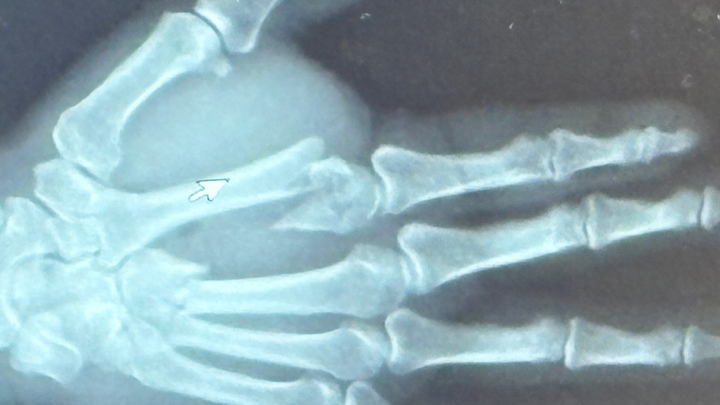

Hello everyone! Not everyone knows this but in September 9, 2025 at about 6pm Chuck had an accident while at work. He was hooking up a grain bagger to a tractor and the hitch of the bagger popped up and smashed Chucks right hand between it and the PTO shaft of the tractor. He had an extensive injury to his hand (which is his dominant hand).

He ended up having basically an emergency surgery that night which went into the next day. He was in surgery for about 2-2 1/2 hours. He now has plates and screws in his hand. Two bones in the top of his hand were affected:

1. The bone leading up to the pointer finger were crushed in 8 places.

2. The bone leading up to the middle finger was broken in 2 places.